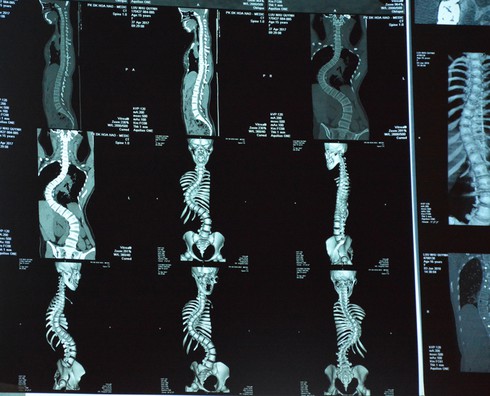

Phim chụp cột sống của bệnh nhân trước khi phẫu thuật |

Ban đầu, bệnh nhân chỉ bị cong 1 đường nhưng dần dần bị cột sống uốn khúc thành 3 đường cong. Các bác sĩ cho biết 3 vùng cong có độ cong 46 độ, 110 độ và 70 độ.